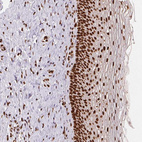

Immunohistochemical staining of human cerebral cortex shows strong nuclear positivity in neurons and glial cells with additional cytoplasmic and nuclear membranous positivity.